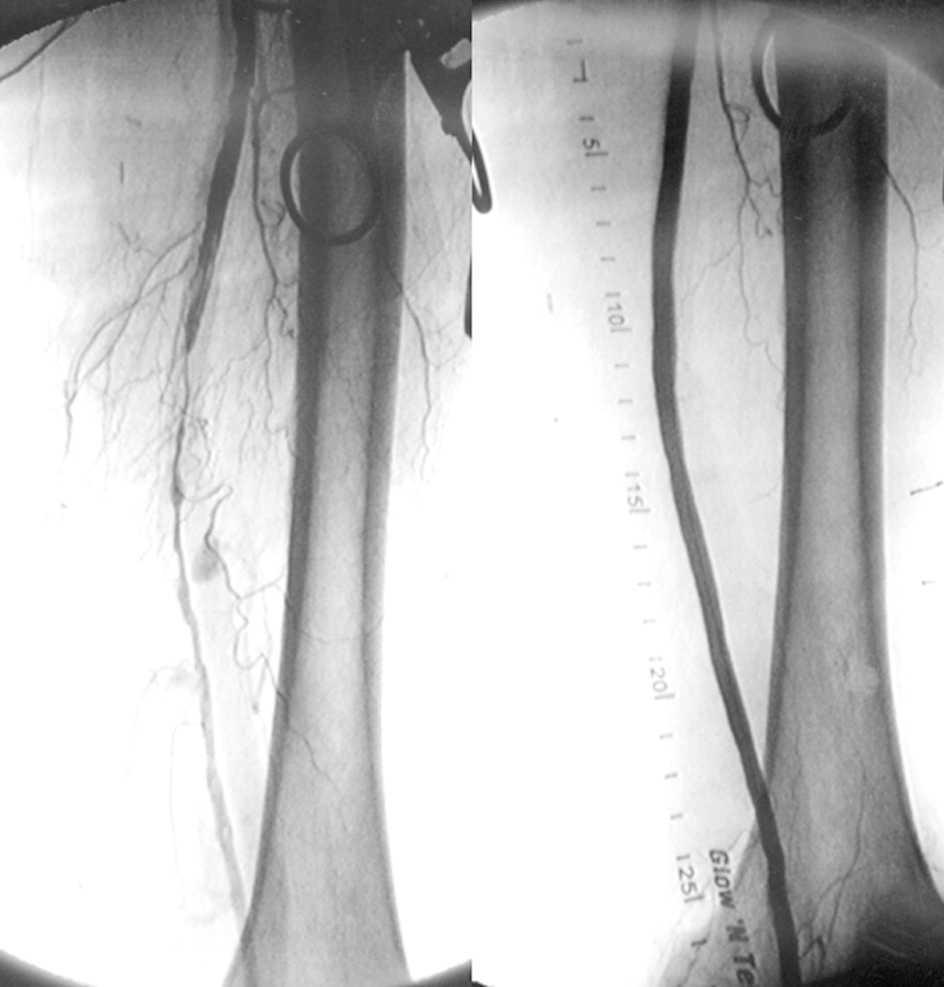

Tratamiento quirúrgico o endovascular de la isquemia severa de miembros inferiores

En pacientes con isquemia crónica y severa que tenían una vena safena adecuada para la revascularización quirúrgica, los resultados fueron significativamente mejores en el grupo quirúrgico que en el grupo de tratamiento endovascular. Para aquellos pacientes que carecían de una vena safena adecuada para la cirugía, los resultados en los dos grupos fueron similares. New England Journal of Medicine, 7 de noviembre de 2022.